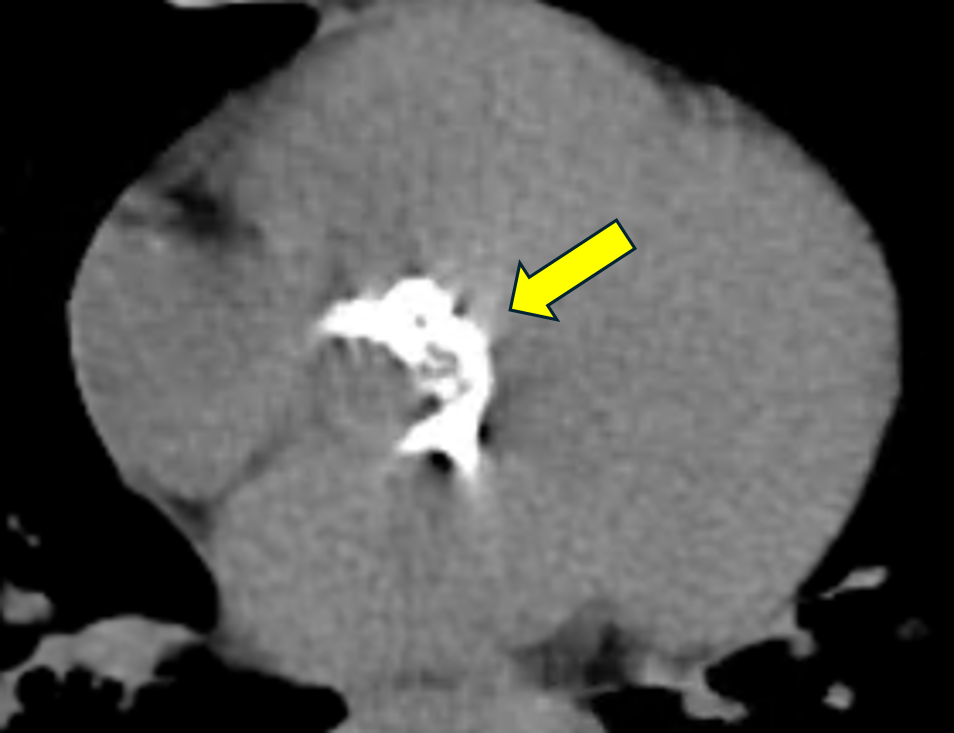

白色的部分皆為嚴重鈣化的瓣膜(正常瓣膜在電腦斷層上無法被看到)。

主動脈瓣由三片瓣葉構成,心臟收縮時開啟,放鬆時閉合,防止血液回流。若瓣膜退化因肥厚、鈣化無法正常開合,因此影響全身血流血流,即為「主動脈瓣狹窄」。